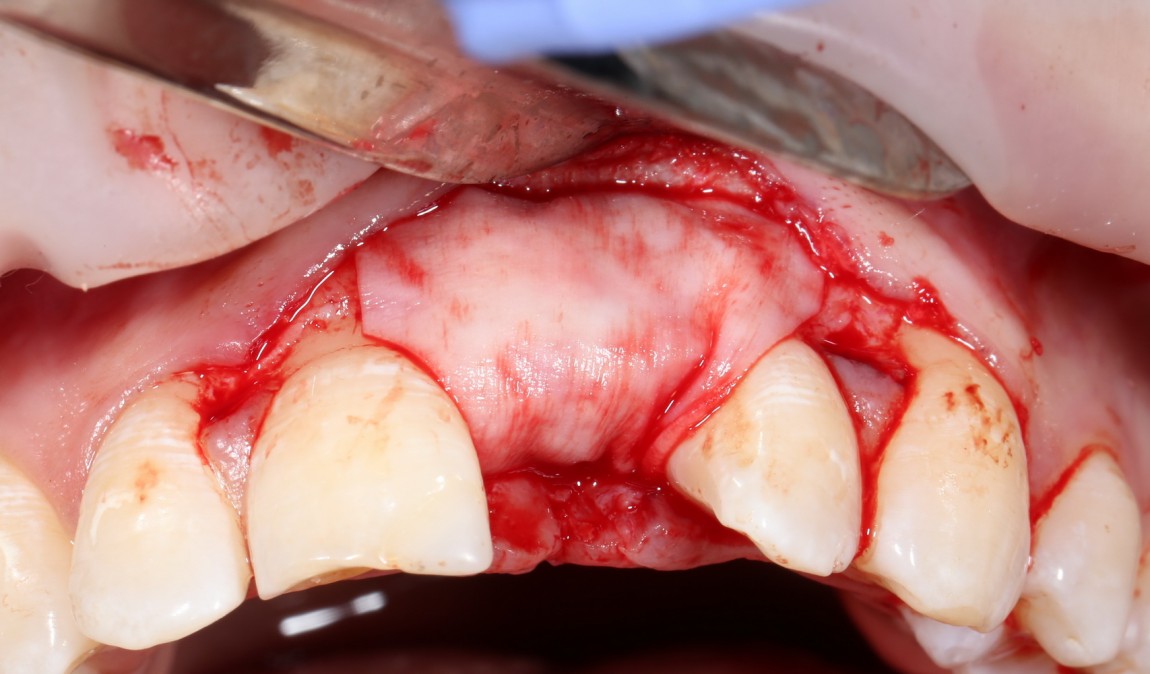

Делаем анестезию, разрез, скелетируем костную ткань:

На фотографиях хорошо видны оставшиеся после удаления объемы костной ткани. Давайте рассмотрим плюсы и минусы текущей клинической ситуации, применительно к нашему плану:

Фактически, альвеолярный гребень атрофировался по толщине примерно наполовину — это минус.

Зато с высотой все в порядке — это плюс

Немедленная нагрузка на имплантат невозможна — это минус. Почему? (см. Факторы…)

Достаточный объем кератинизированной десны, который даст нам возможность герметично запечатать послеоперационную рану — это, несомненно, тоже плюс. (вспомним факторы успеха остеопластической операции, часть III)

Ну и, оставшиеся объемы костной ткани позволят нам установить и правильно позиционировать имплантат — это главный плюс. А значит, мы обойдемся одной операцией вместо двух.